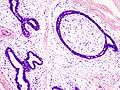

Fibroadenoma Histology (H&E). The image demonstrates intracanalicular morphology (top right) and pericanalicular morphology (bottom left)

Histopathologic image of breast fibroadenoma. Core needle biopsy. Hematoxylin & eosin stain.

Fibroadenoma of the breast is a benign tumor composed of a biphasic proliferation of both stromal and epithelial components that can be arranged in two growth patterns: pericanalicular (stromal proliferation around epithelial structures) and intracanalicular (stromal proliferation compressing the epithelial structures into clefts).

These tumors characteristically display hypovascular stroma compared to malignant neoplasms.[2][5][8] Furthermore, the epithelial proliferation appears in a single terminal ductal unit and describes duct-like spaces surrounded by a fibroblastic stroma. The basement membrane is intact.[11]